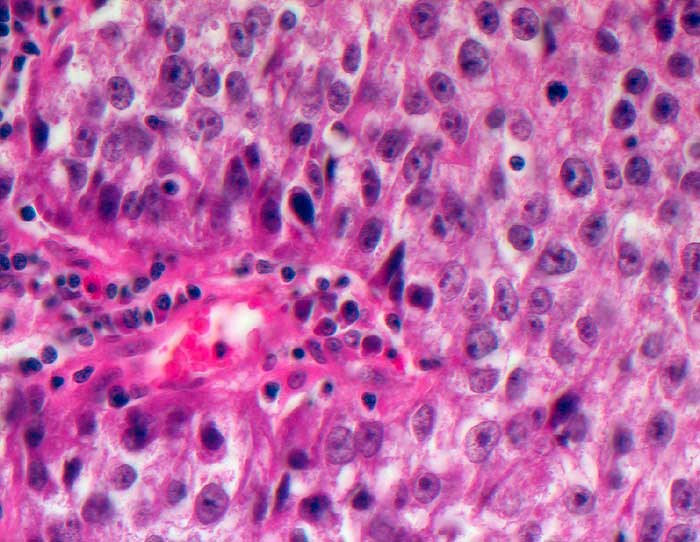

PathoPic ID 5611 - Adenokarzinom der Prostata

Adenokarzinom der Prostata

maligner Tumor

Prostata

Genitalorgane, männlich

Solide Tumormasse aus grossen polygonalen Tumorzellen mit auffallenden Nukleolen.

Histologie

400

67

männlich